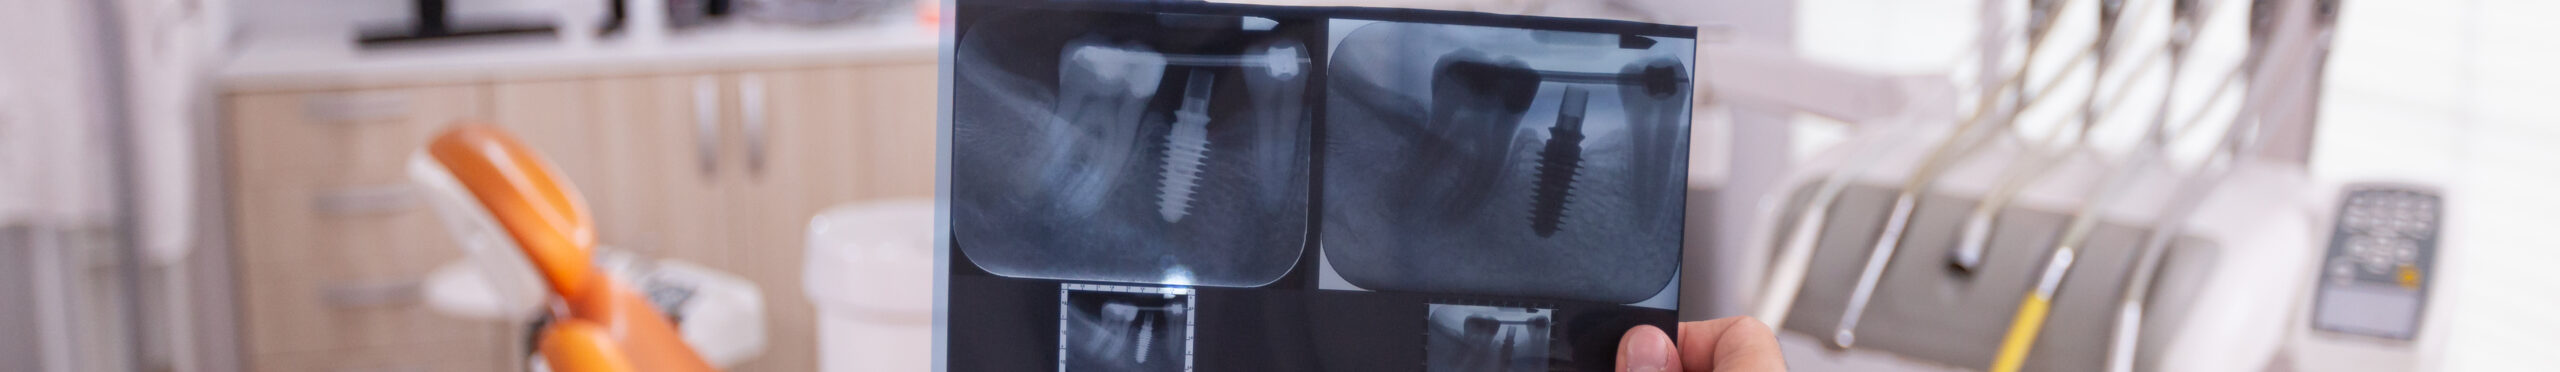

КЛКТ расшифровывается как конусно-лучевая компьютерная томография зубов. Это один из методов рентгеновской диагностики, который дает возможность получить трехмерное изображение зубочелюстной системы в разных проекциях.

3D томография зубов (КЛКТ)

3. 3D-снимок (КЛКТ). Дает возможность получать трехмерную модель зубов или определенного участка челюстно-лицевой области. Врач может строить любое сечение, выполнять с точностью до миллиметра требуемое измерение. Это самый информативный метод, так как дает информацию о состоянии челюсти и зубов сразу в трех проекциях. В специальной программе можно точно измерить расстояние до пазухи, оценить плотность кости.